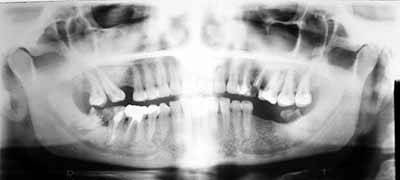

OPG

(Orthopantomogram) and Cephalogram |

What is OPG?

OPG stands for Orthopantomography. It is a special

method for obtaining radiographs of the teeth-bearing

jaws, both upper and lower.

How is it different from regular X-ray machines?

A regular X-ray machine cannot take detailed pictures

of the jaw-bones. An OPG machine is specially constructed

so that it rotates around the jaw-bones, thus giving

us an extremely good idea about the structure of the

jaw bones. Yes, x-rays are used, but the method is

totally different.

In what situations are they needed?

OPG x-rays are usually asked for by dentists, whether

they be general dentists, orthodontists, oral surgeons

or prosthodontists/implantologists. Because OPGs give

a bird-eye view of the teeth and the adjacent bones,

they are useful in a wide-variety of conditions including

infections, tumors, congenital abnormalities, pre-implant

evaluation and trauma.